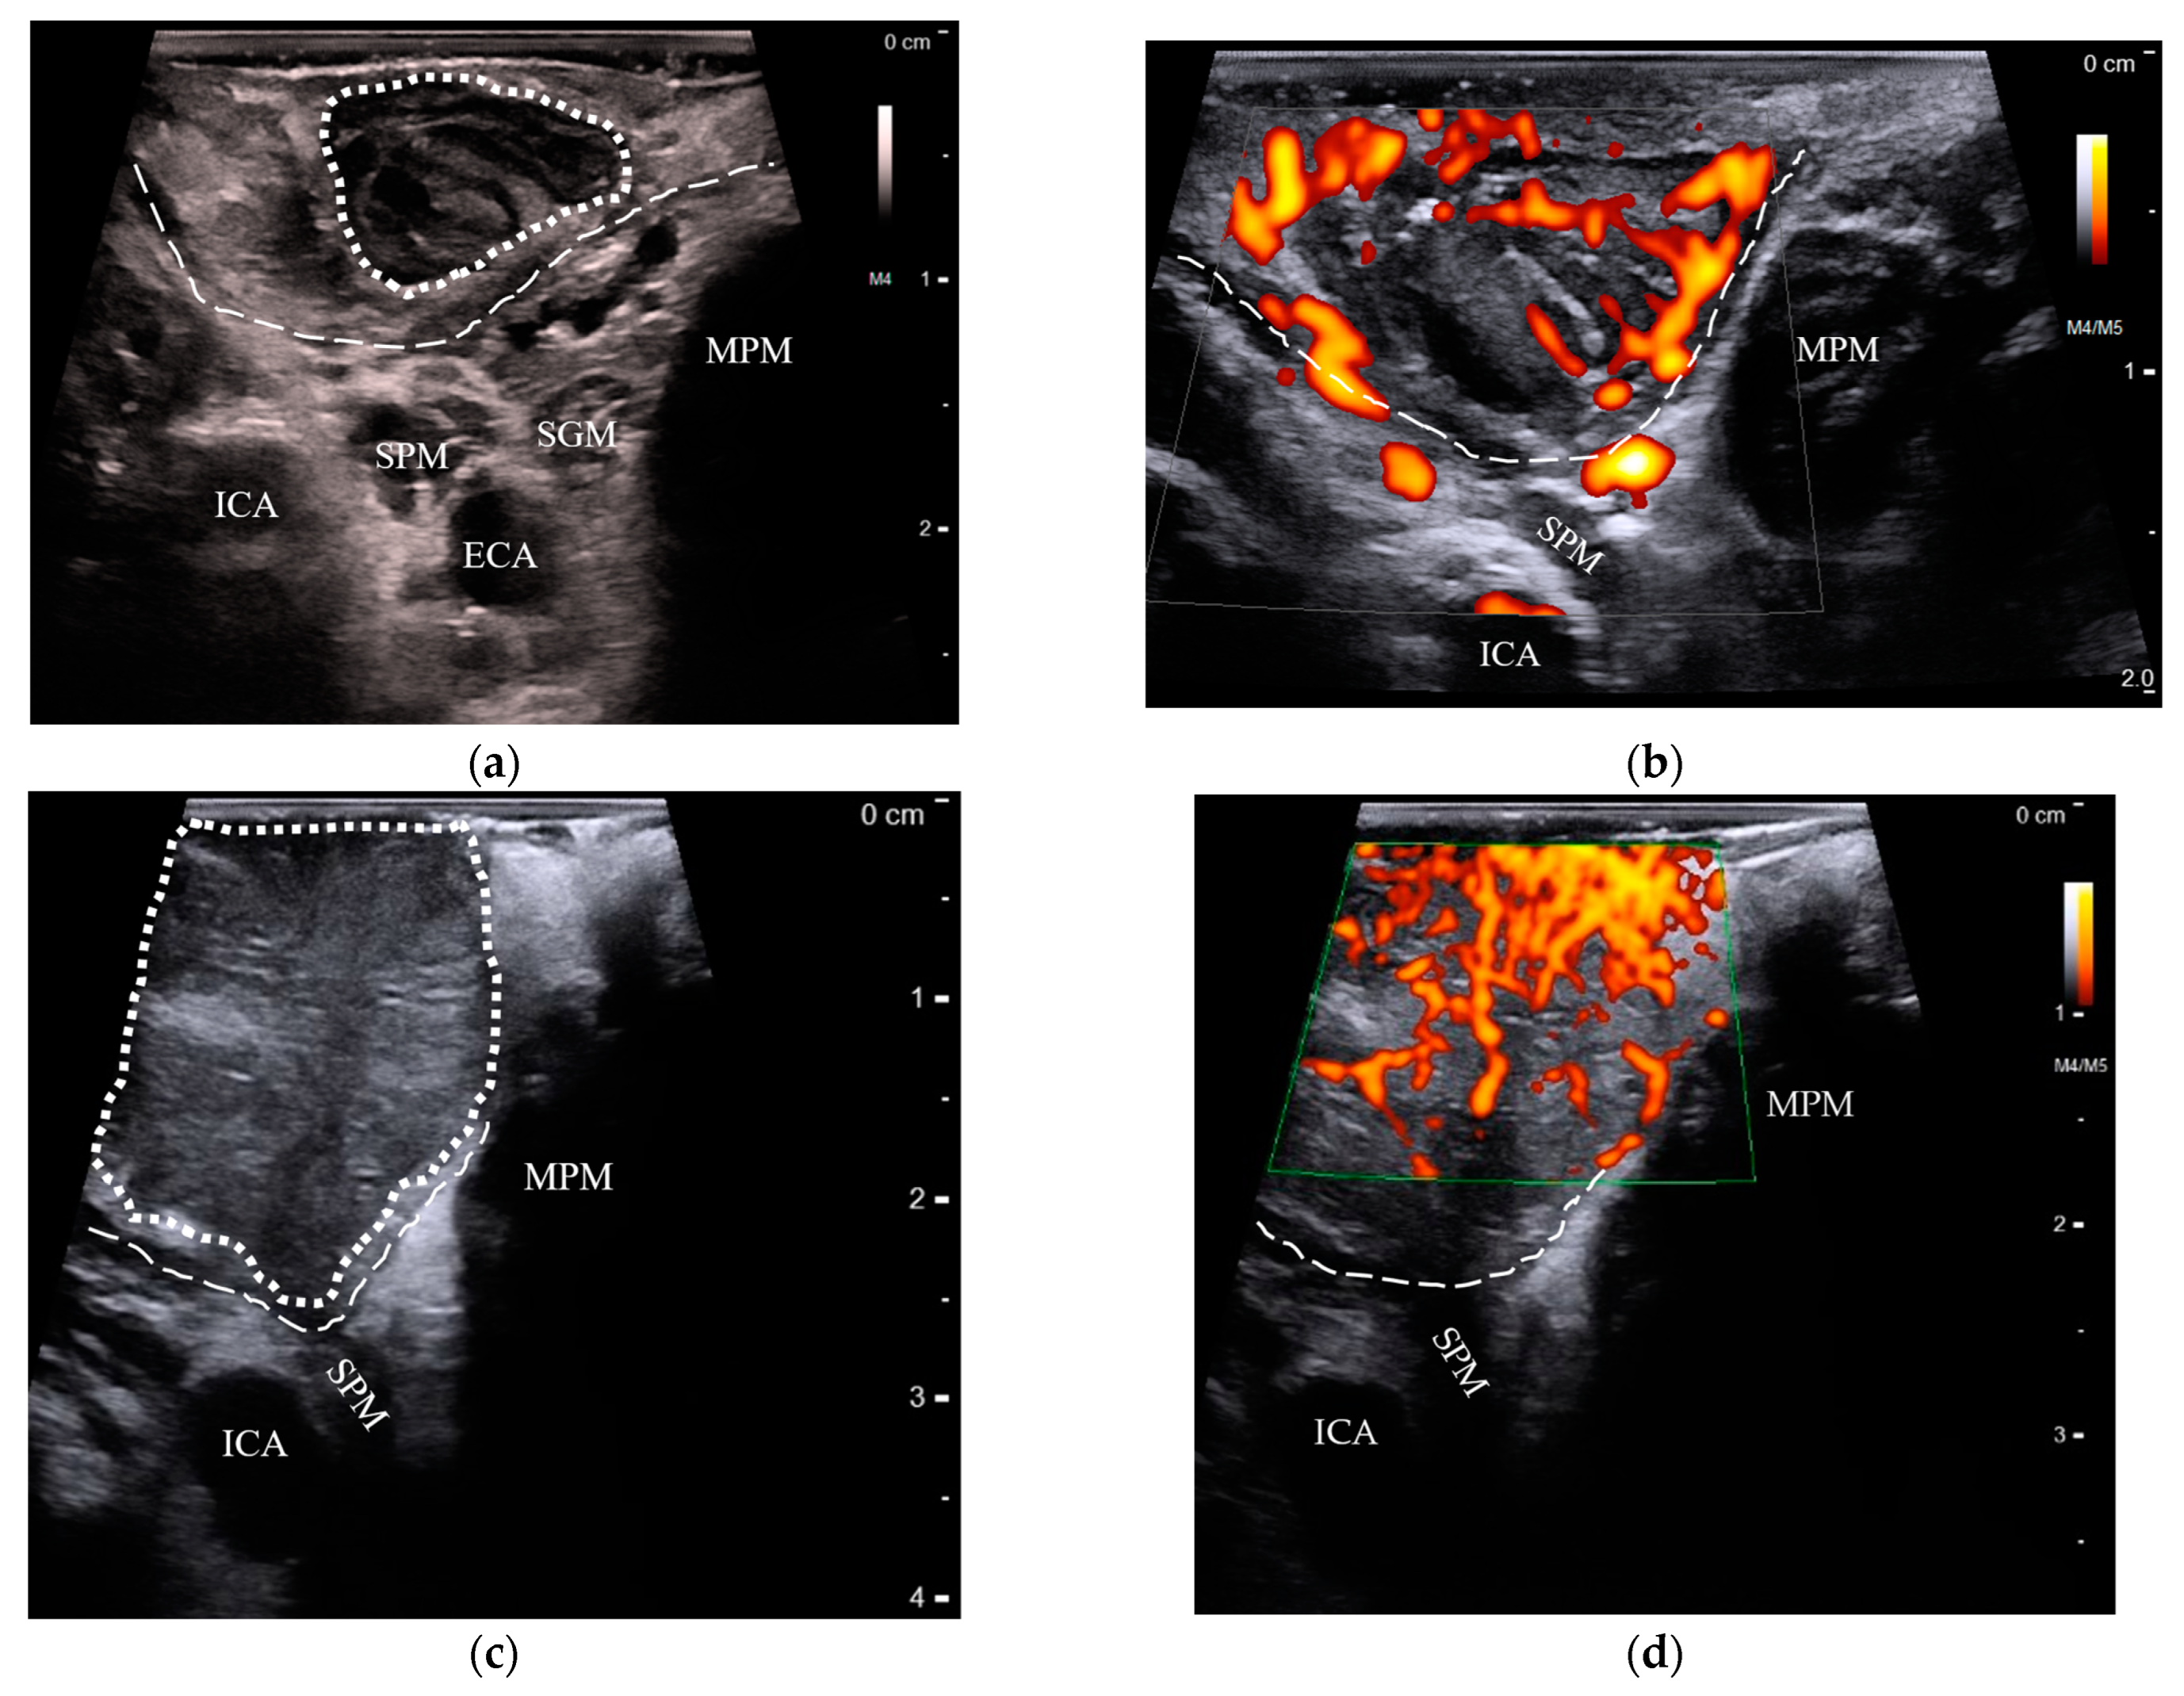

US and MRI test results are shown in Table 1. Transoral US of the palatine tonsils could be performed in all patients with suspected palatine tonsil cancers (n = 21), while only one patient could tolerate transoral US of the lingual tonsil. Instead, we performed transcervical US of the oropharynx in the remaining four lingual tonsil cases. Tumors of the palatine tonsils could be distinguished from the contralateral tonsils due to increased size, loss of striated appearance, and chaotic doppler flow (Figure 2, Video S1).

Figure 2.

Comparison of transoral US features in benign and cancerous palatine tonsils: (a) a normal palatine tonsil (dotted outline) with striated crypts overlying the constrictor muscle (dashed line), lying superficially to the stylopharyngeus muscle (SPM), styloglossus muscle (SGM), medial pterygoid muscle (MPM), internal carotid artery (ICA), and external carotid artery (ECA); (b) power doppler shows the palatine tonsils’ blood flow originating from the constrictor muscle and branching outward parallel to the crypts; (c) a stage-T2 palatine tonsil HPV+ SCC appears as an enlarged, hypoechoic mass without crypt striations (dotted outline), but respects the boundaries of the constrictor muscle (dashed line); (d) with power doppler, the same tumor is seen with random, chaotically increased blood flow. US: ultrasound; HPV+ SCC: human papillomavirus-positive squamous cell carcinoma.